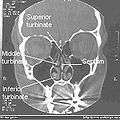

In anatomy, a nasal concha (/ˈkɒnkə/), plural conchae (/ˈkɒnki/), also called a turbinate or turbinal, is a long, narrow, curled shelf of bone that protrudes into the breathing passage of the nose in humans and various animals. The conchae are shaped like an elongated seashell, which gave them their name (Latin concha from Greek κόγχη). A turbinate bone is any of the scrolled spongy bones of the nasal passages in vertebrates.[1]

Turbinates are composed of pseudostratified columnar, ciliated respiratory epithelium with a thick, vascular, and erectile glandular tissue layer. [2] The turbinates are located laterally in the nasal cavities, curling medially and downward into the nasal airway. Each pair is composed of one turbinate in either side of the nasal cavity, divided by the septum.[2]

The superior turbinates are smaller structures, connected to the middle turbinates by nerve-endings, and serve to protect the olfactory bulb. The openings to the posterior ethmoidal sinuses exist under the superior meatus.[1]

The middle turbinates are smaller. In humans, they are usually as long as the little finger. They project downwards over the openings of the maxillary and anterior and middle ethmoid sinuses, and act as buffers to protect the sinuses from coming in direct contact with pressurized nasal airflow. Most inhaled airflow travels between the inferior turbinate and the middle meatus.[1]

The inferior turbinates are the largest turbinates, and can be as long as the index finger in humans, and are responsible for the majority of airflow direction, humidification, heating, and filtering of air inhaled through the nose.[1]